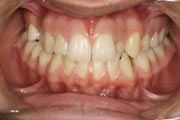

Crowding

Before